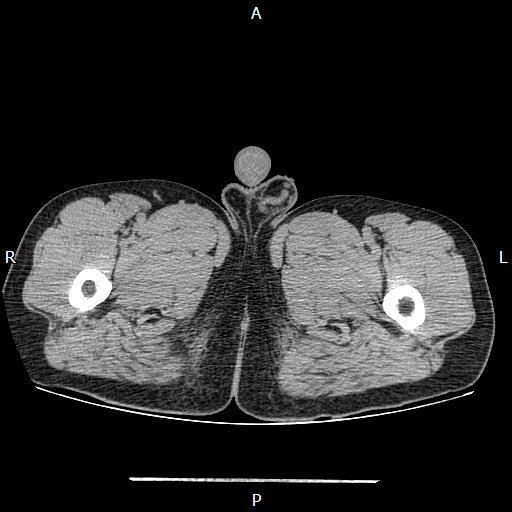

CT检查提示右侧阴囊空虚

胸外科主任方震宇随即邀请泌尿外科林华主任医师进行联合会诊。专家指出,未降入阴囊的隐睾发生癌变的风险远高于正常睾丸。鉴于患者已完成生育,从远期健康安全考虑,有必要对隐睾进行处理。经团队审慎评估并与患者及家属充分沟通后,最终制定了个体化的手术方案,拟在一次麻醉下,利用腹腔镜微创技术,同时实施左侧腹股沟疝修补术与右侧隐睾探查切除术。